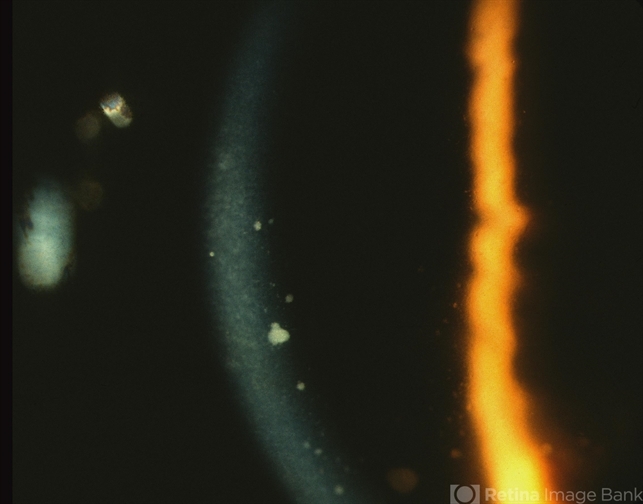

- Sarcoidosis Panuveitis

- Photo slit lamp biomicroscope

- 50-year-old African American women presented with decreasing vision in both eyes and floaters in the left eye. She had a history of asthma and sub-cutaneous skin nodules. Anterior segment examination reveal keratic precipitate on the corneal endothelium.